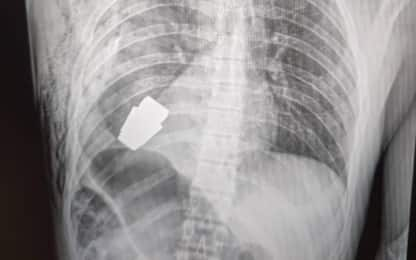

Ucraina, intervento per estrarre granata dal petto di un soldato Mondo L'operazione, unica nel suo genere, ha coinvolto anche gli artificieri che hanno avuto il compito... 12 gen - 18:10